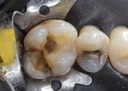

Joe Cha #18 prep

Alan Chinn #2 pre-op